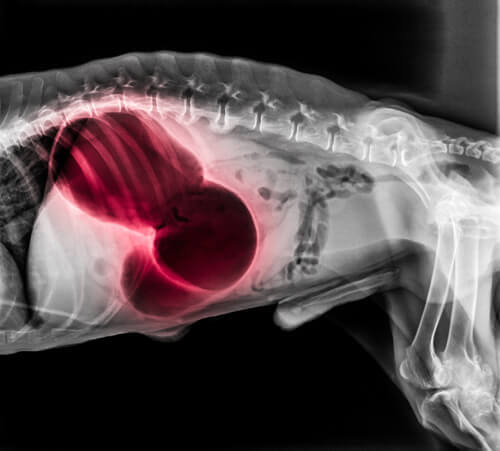

W przypadku wystąpienia w okolicy serca lub płuc

W tych obszarach zakrzep może prowadzić do wielu bardzo poważnych objawów ogólnoustrojowych. Mogą to być omdlenia, duszności i paraliż. Mogą wystąpić blade lub niebieskie dziąsła, niezdolność do snu lub odkrztuszanie krwi. Zatorowość płucna jest zwykle śmiertelna.